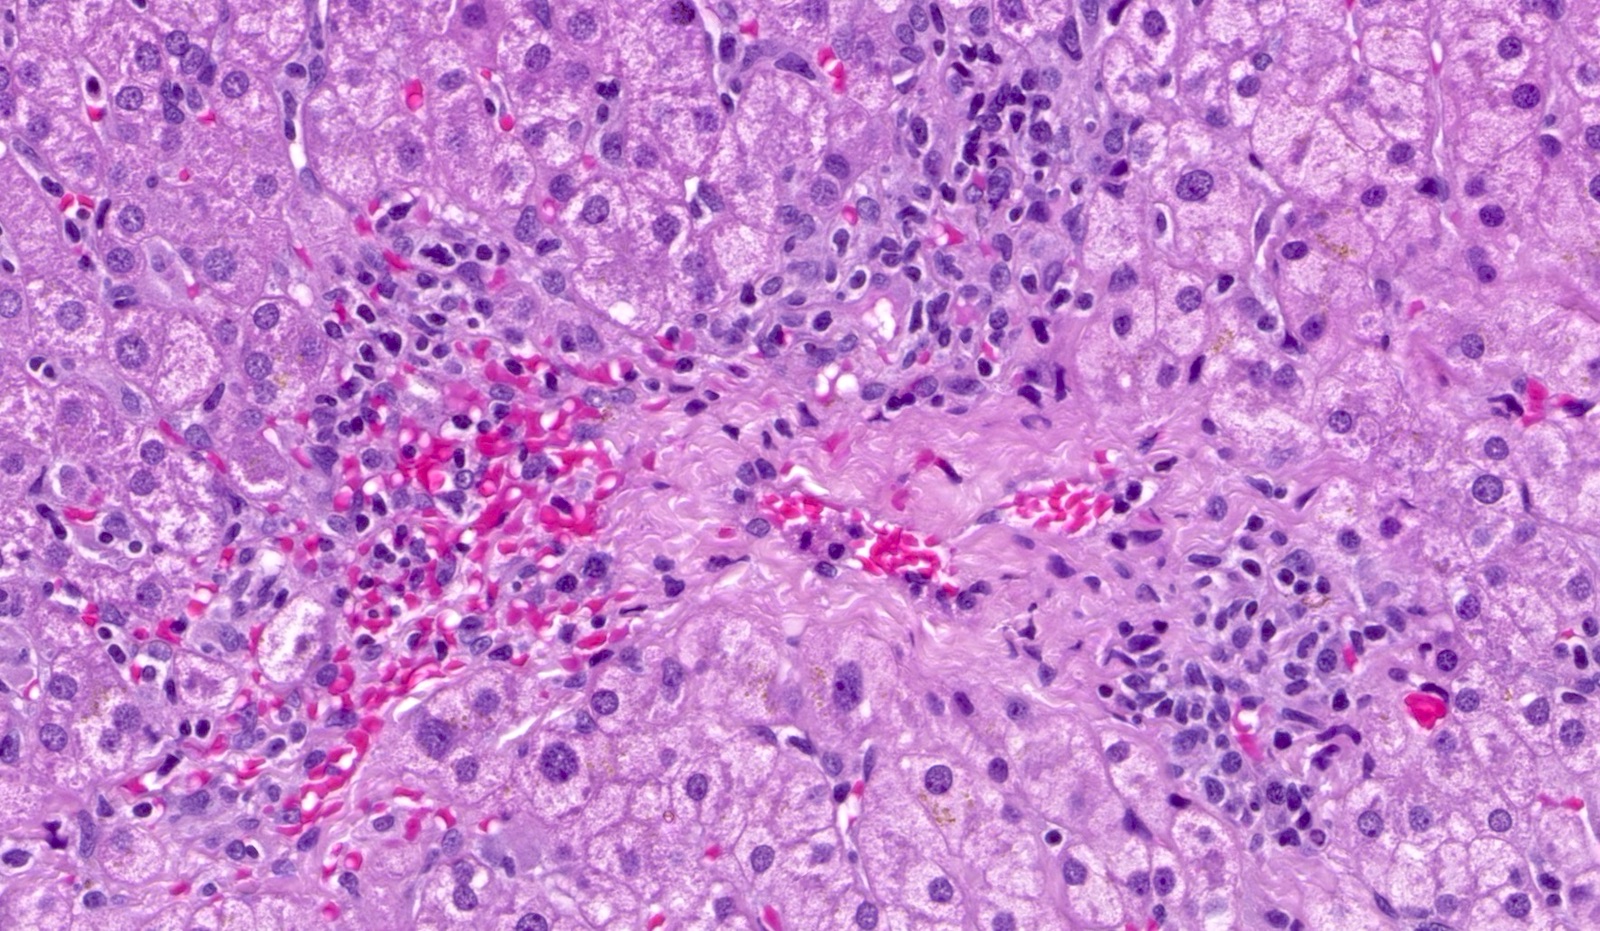

- Inflammation (Clin Transplant 2018;32:e13227, Liver Transpl 2016;22:1593, Liver Transpl 2018;24:897):

- Chronic hepatitis pattern of mononuclear inflammation with interface hepatitis or lobular and perivenular inflammation

- Perivenulitis

Microscopic (histologic) images